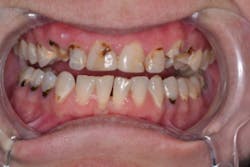

I knew Sarah when she was well and could smile at the world. Then, when the painful loss of a loved one dismantled her life, having no safety net or support, depression set in. Later, substance abuse took over, and eventually Sarah hit rock bottom. Thankfully, a local family took her in, and she is reclaiming her life. But her teeth and smile were devastated (figures 1 and 2).

Traditional treatment options would be full-mouth reconstruction (FMR) or full-mouth extractions and dentures. There were only a few teeth in her mouth that did not have advanced decay, so FMR would necessitate root canals, build-ups, and porcelain restorations. With limited finances and a history of neglect, most practitioners might be inclined to write off the patient and prepare her for dentures, and the thought entered my mind as well. Having known Sarah during happier times, however, I wanted something better for her. But what type of restorative treatment should I attempt?